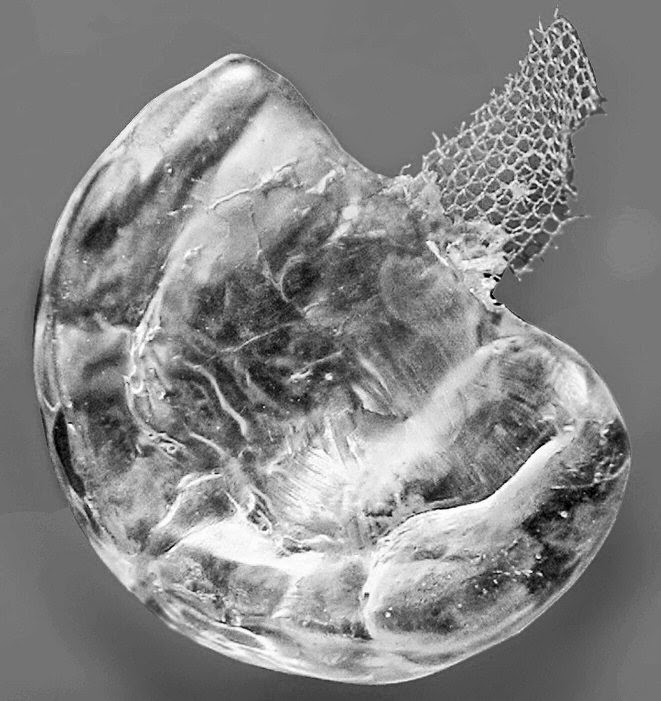

In this article, Karayazgan, Gunay, Gurbuzer, & Erkan, (2008) introduce the use of a familiar treatment method for infants with cleft palate: the use of a nasopharyngeal obturator. However, the obturator that is being presented in this article is different from the conventional appliance. This obturator uses tulle: a soft, durable fabric, in place of the traditional rigid material that is most often used.

use of tulle to connect the bulb and plate of the obturator is cost efficient

and will most likely not cause as much, if any, irritation or damage to the

soft tissue in the mouth.

et al. (2008) claim that the use of tulle in a nasopharyngeal obturator is a

cost efficient and viable option for infants with cleft palate defects. Tulle

is durable, flexible and helps an infant to feed more efficiently by imitating

the function of the velum. Using this material is a valuable resource for aiding